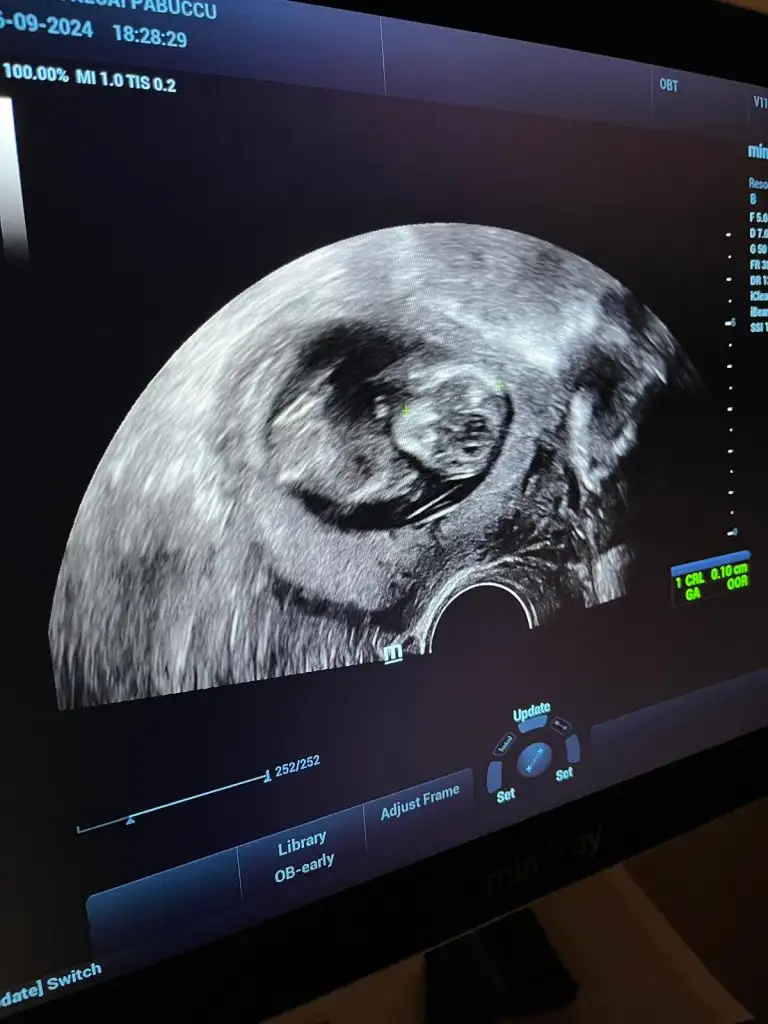

Benim minnoşa da bak teyzesiErkek oldu kız

İnşallah ya devlet hastanesinde ultrasonları çok kötü bugün hastaneye gittim korktum kalp atışını bile zor duyuruyorlarPamuğum sanki erkek gibi geldi bana, teyzoşu onu yesin. Sağlıcakla gelsin inşallah bebişlerimiiiiz

Niye korktun kiİnşallah ya devlet hastanesinde ultrasonları çok kötü bugün hastaneye gittim korktum kalp atışını bile zor duyuruyorlar

Ya sesi çıkmıyor ultrasonun sanki kalp atışı yokmuş gibi çok kötüydü zaten ultrasonda da çok kötü görünmüyor kesesi de kendisi de bulanık görünüyor o yüzden özeller şuan en iyisiNiye korktun ki

Ya sesi çıkmıyor ultrasonun sanki kalp atışı yokmuş gibi çok kötüydü zaten ultrasonda da çok kötü görünmüyor kesesi de kendisi de bulanık görünüyor o yüzden özeller şuan en iyisAllah korusun kendini korkutma